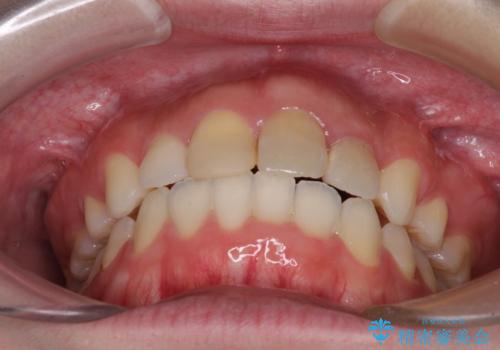

抜歯矯正の後戻り インビザラインによるオープンバイトの再矯正

- 以前矯正治療をされていましたが、後戻りが起きたことを気にして来院された患者様です。

上下前歯のオープンバイトを改善するため、インビザラインにて治療を行うこととしました。

外食が楽しみである患者様だったので、インビザラインによる治療期間は我慢の時期であったようです。

自己管理を徹底していただいたので、1年程度で治療を終えることができました。